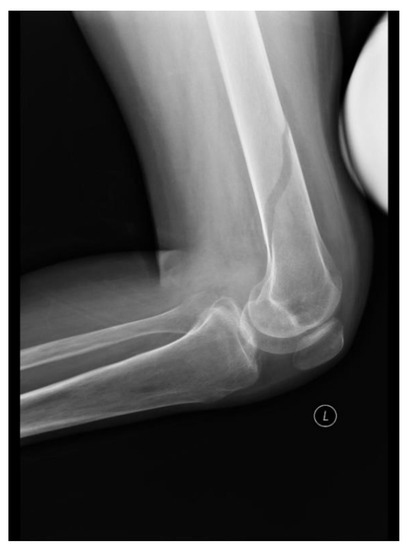

| 4 | 30 | 63 months | C5 | Paresis of upper limbs, paraplegia | Spastic (MAS 3/4) | 2900 | Fracture |